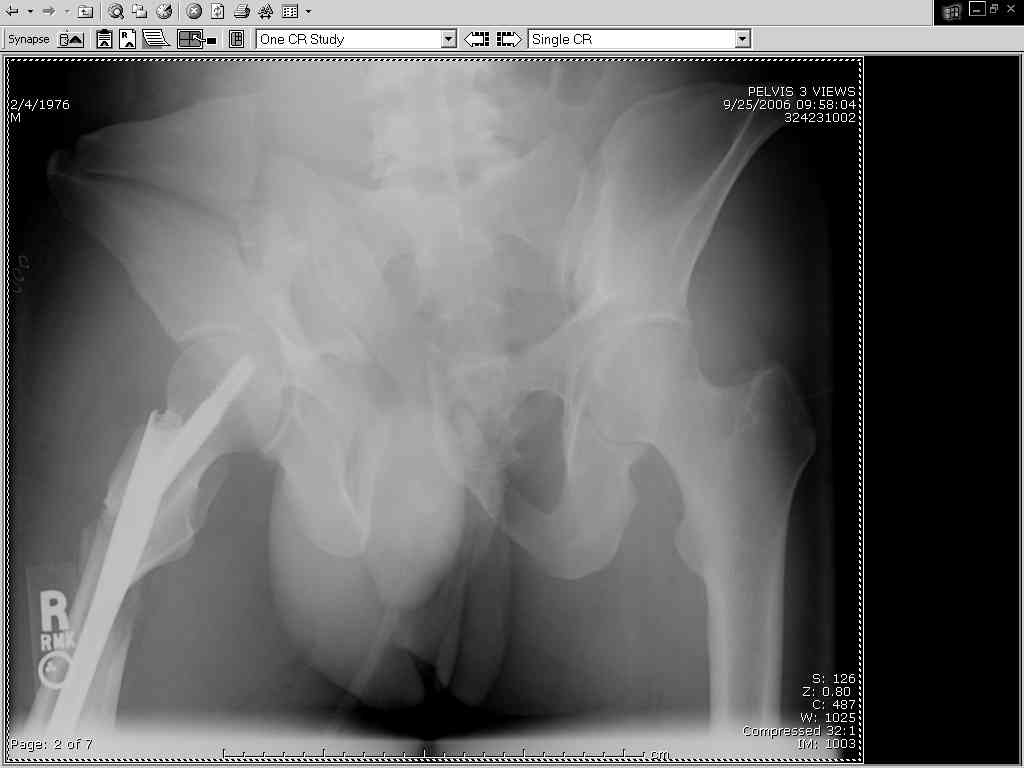

I'm not sure I'd call it an APC 3. But whatever you call it, you still need to fix it, right?

Thanks Adam - I agree it's not a pure APC (is there really such thing as a pure force vector strictly in the x,y or z plane?). I stand corrected. Maybe a hybrid APC (ext rot of L hemipelvis, symphysis disruption, ext rot of R anterior innominate) plus vertical shear as well with 3 or-so cm of cephalad migration of the R ilium. Maybe just "C-type".....

It almost looks to me like an extra-articular both column fx, in addition to the pelvic component. It has the typical triangular fragment and the OO view has a hint of the spur. You may be able to get it all with plates. I would consider fixing the crest first, then a long plate for both symph and iliac portion. SI may close with reduction of symphisis. Looks like the inferior portions are intact. I like your plan as well. You will probably solicit lots of opinion. Good luck. Look forward to post op view.